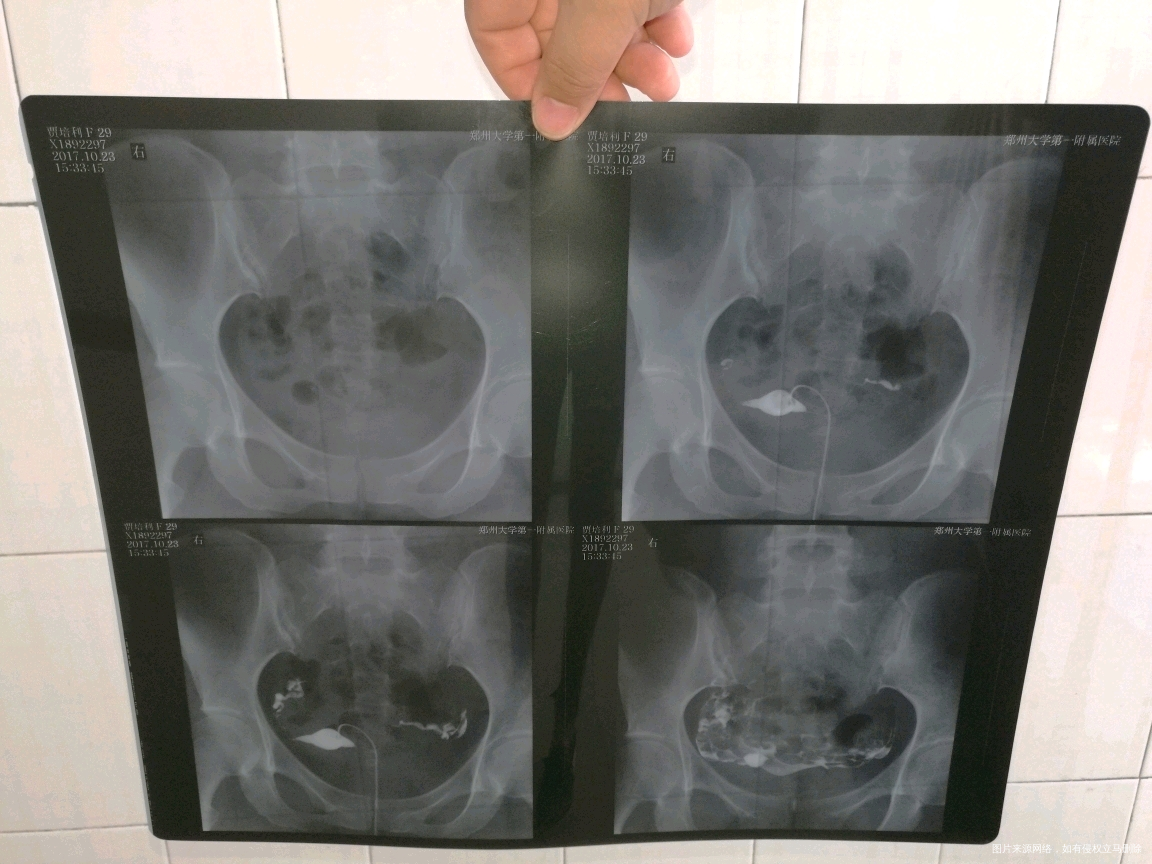

排卵试纸是阳,怎么安排同房受孕率高,为什么一直都是右侧有优势卵泡,左侧没有,但是我右侧输卵管有点上举。

你好,右侧输卵管问题需要解决,否则即使有好卵泡,也不好受孕

补充说明:1 一直右侧排卵,如果每个月都监测,移都是右侧,那么左侧卵巢功能功能真的很不好,如果是隔开检查卵泡的,那可能左侧排卵比较稀发或是正好错过了。 2 目前右侧卵泡还不到成熟,(接近成熟卵泡1.8--2.5之间,排卵后内膜0.8--1.0 ),但是右侧输卵管上举,真的影响怀孕,如果不解决这个问题,即使有不错的卵泡与内膜,也会降低好孕几率的,规范治疗2--3个月后复查一下为好。近期隔日同房,可以试孕这个周期,3 祝你好孕。如果我的建议对您有帮助,请记得选择点击采纳哦。